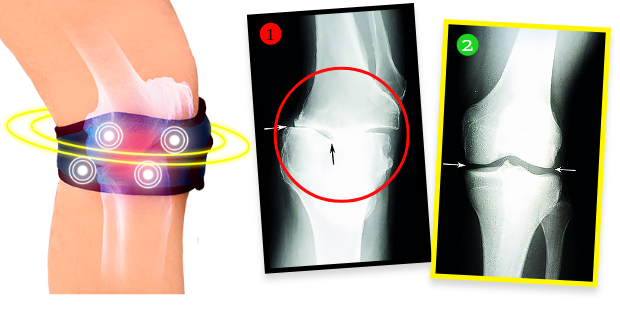

Gospođa Helena je posle terapije uradila RTG i ispostavilo se da su se degenerativne promene na kolenu potpuno povukle! Lekar je zanemeo – nije znao šta da kaže. A činjenice su sledeće: zahvaljujući biomagnetnoj traci, stanje kolena gospođe Helene ne samo da je prestalo da se pogoršava. Hrskavično tkivo i osetljive strukture u predelu zgloba regenerisali su se, a koleno se vratilo u potpuno funkcionalno stanje kakvo je imalo pre mnogo godina. Traka, naime, emituje prirodno i bezbedno biomagnetno polje koje prodire u najdublja tkiva zgloba, hrani i regeneriše hrskavicu, vraća joj elastičnost i gipkost, a takođe podstiče proizvodnju sinovijalne tečnosti, koja amortizuje pokrete i štiti od bolnog trenja pri kretanju. Ovo je potpuno neinvazivna i bezbedna terapija.